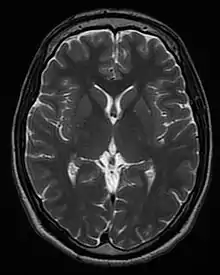

) of those nuclei after the pulse sequence, and often on other parameters discussed under specialized MR scans. Contrast in most MR images is actually a mixture of all these effects, but careful design of the imaging pulse sequence allows one contrast mechanism to be emphasized while the others are minimized. The ability to choose different contrast mechanisms gives MRI tremendous flexibility. In the brain, T1-weighting causes the nerve connections of white matter to appear white, and the congregations of neurons of gray matter to appear gray, while cerebrospinal fluid (CSF) appears dark. The contrast of white matter, gray matter and cerebrospinal fluid is reversed using T2 or T*

2

imaging, whereas proton-density-weighted imaging provides little contrast in healthy subjects. Additionally, functional parameters such as cerebral blood flow (CBF), cerebral blood volume (CBV) or blood oxygenation can affect T1, T2, and T*

and so can be encoded with suitable pulse sequences.